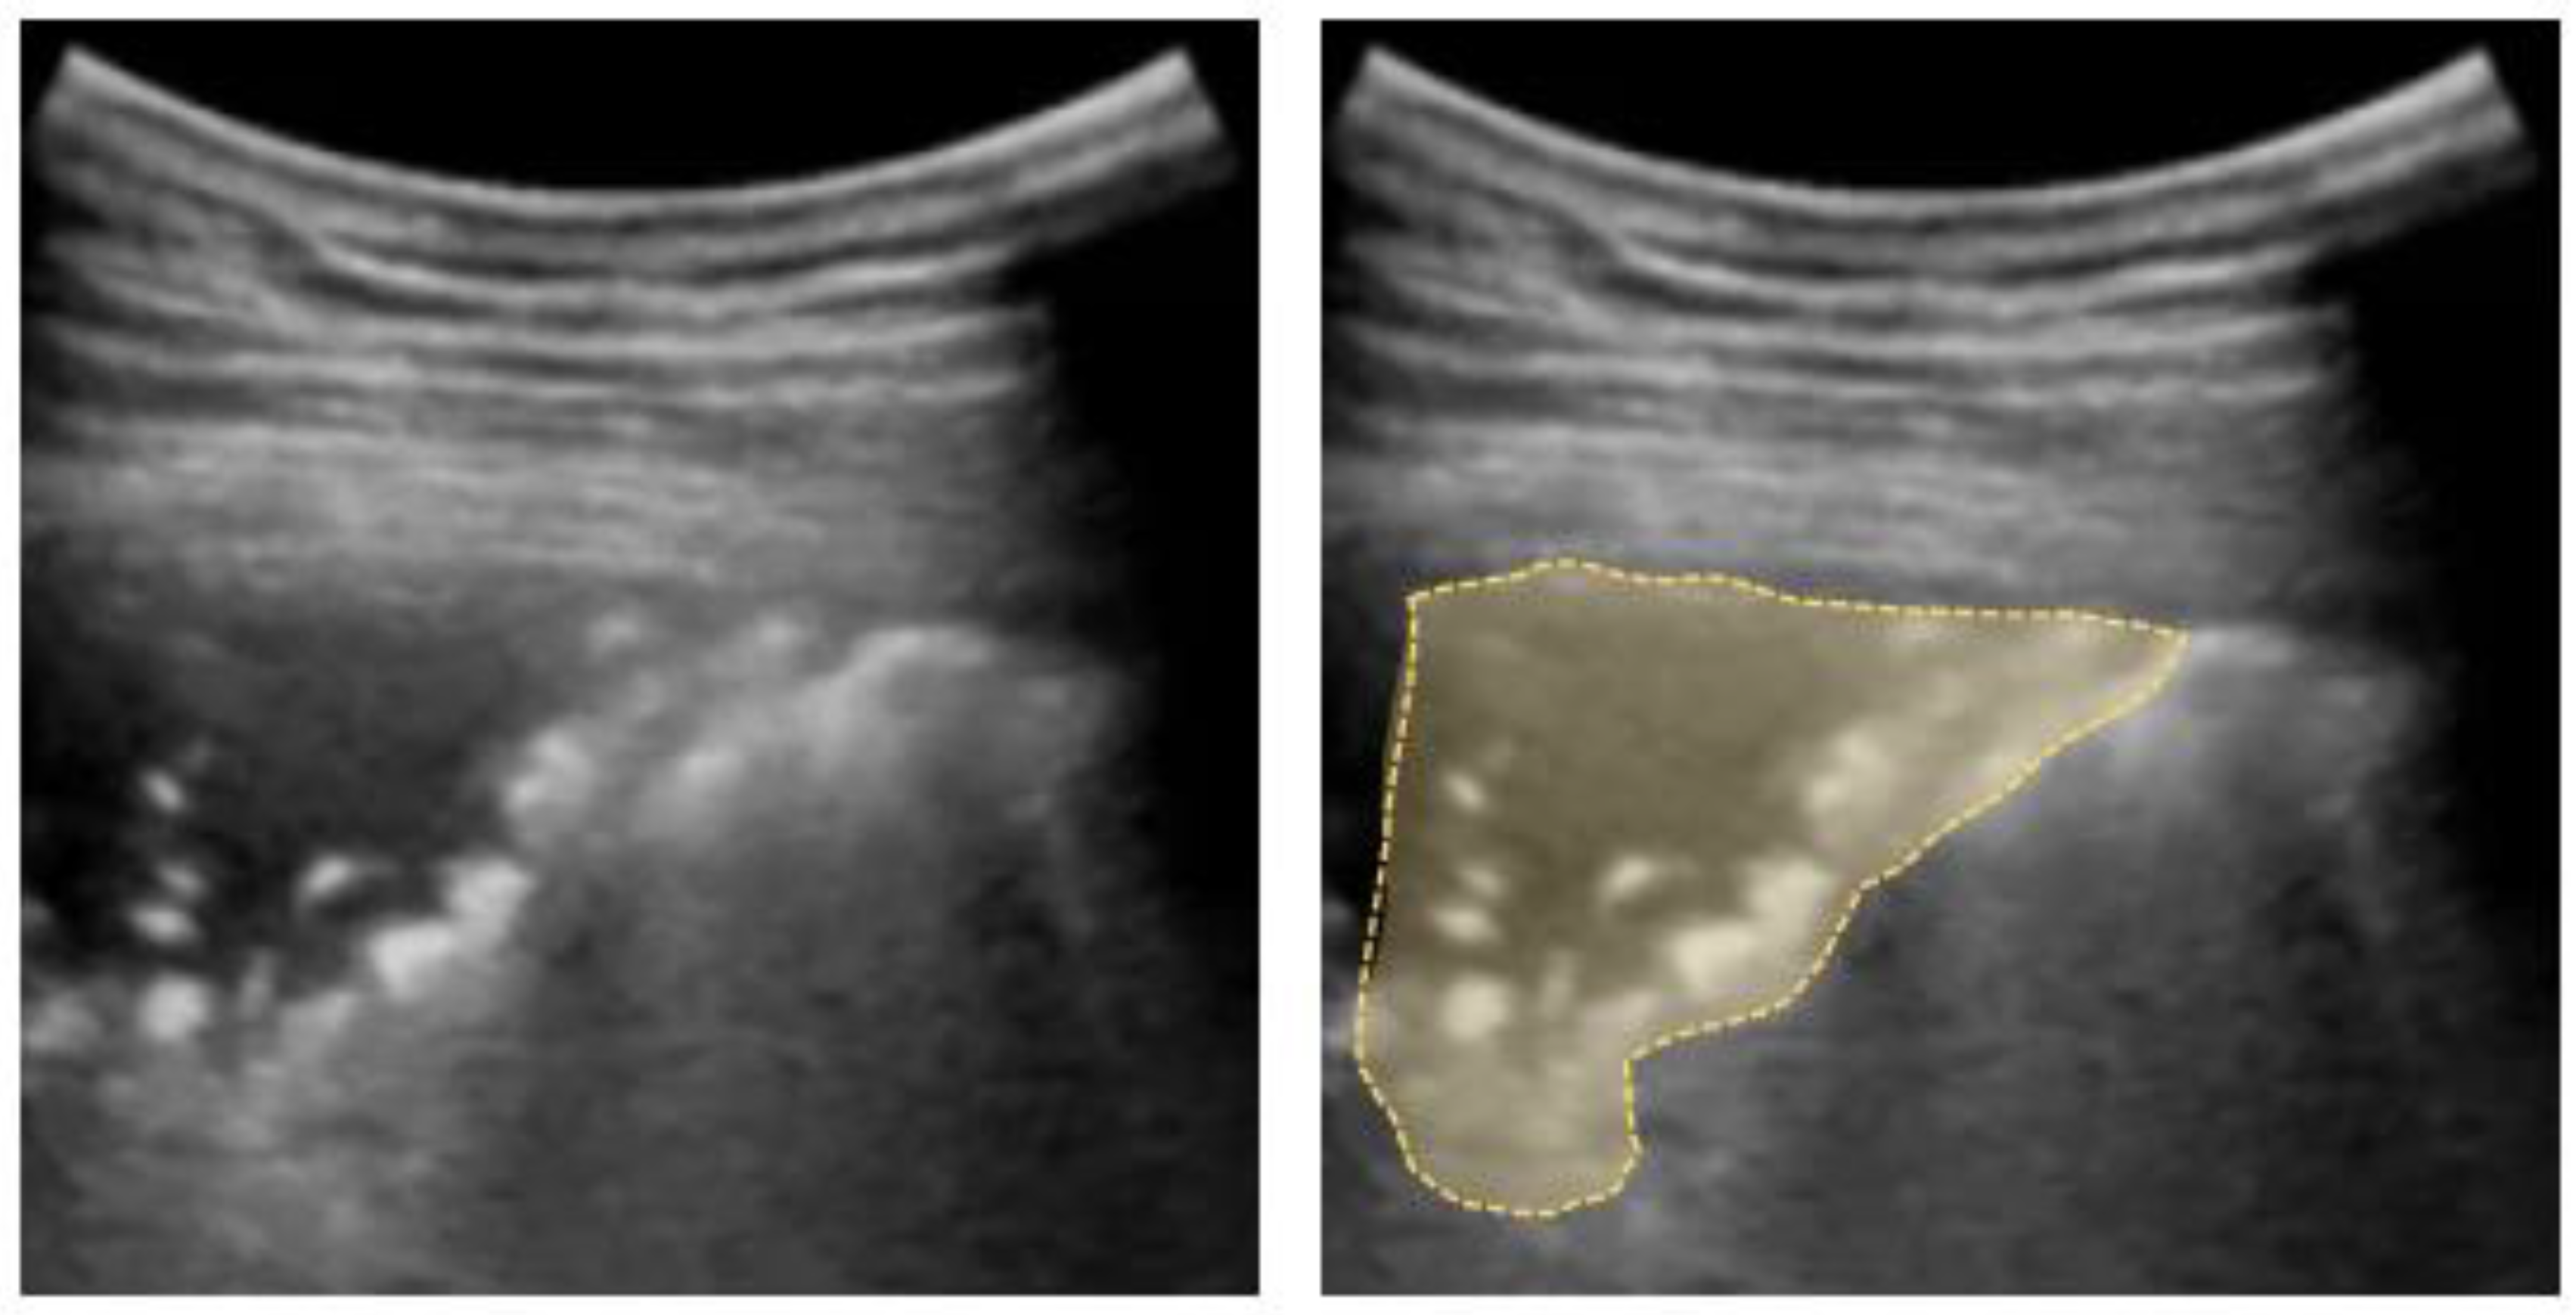

4.4. Pleural Effusion